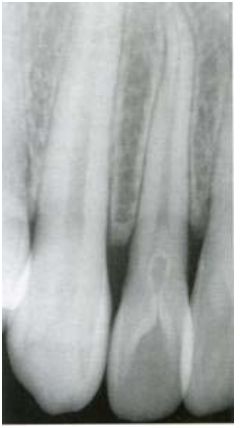

根據下面這張根尖 X 光片顯示之上顎側門齒,最佳的診斷為下列何者?

(A)齒上齒(dens evaginatus)

(B)齒中齒(dens in dente)

(C)爪形咬頭(talon cusp)

(D)牛型齒(taurodontism)

x光上: inverted teardrop shape